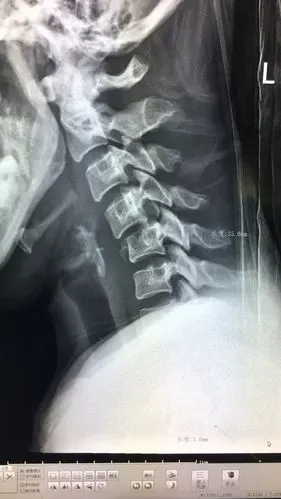

脖子骨折

我科自主完成第一例颈椎骨折脱位前路手术